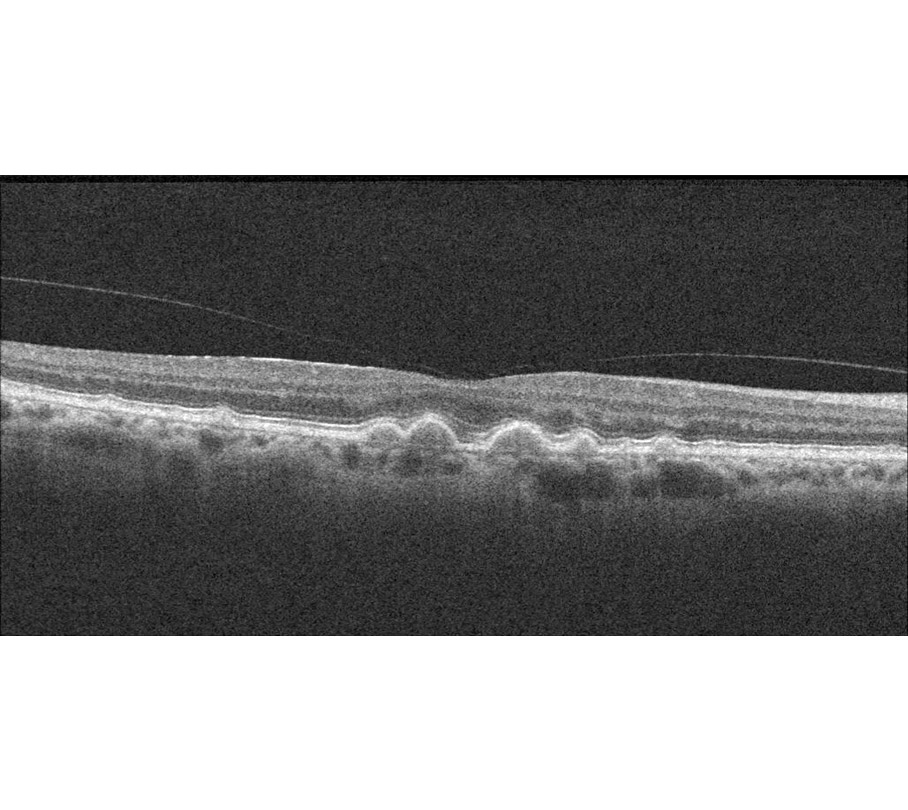

Stacks Image 602324

feuchte AMD im OCT: Ödem in der tieferen Netzhaut

Wann ist die Makula trocken, wann feucht?

Wenn sich wegen Sauerstoffmangel unter der Netzhaut durch Aussprossung aus den Aderhautgefäßen neue Gefäße bilden, treten aus den undichten Wänden der neuen Gefäße Flüssigkeit und Blut aus (s. o. im Film). Die tieferen Netzhautschichten schwellen durch diese Flüssigkeitsansammlung an. Es entsteht ein Netzhautödem und manchmal, aber nicht immer, werden Blutungen auf der Netzhautoberfläche sichtbar. Diese Blutungen sind mit dem Augenspiegel sichtbar, nicht aber die zugrundeliegende Membran aus neugebildeten Gefäßen aus der Aderhaut. Die feuchte AMD ist daher am besten durch die OCT (optische Kohärenztomographie) erkennbar, da sie auch die tieferen Schichten der Netzhaut (Ödem) sichtbar macht. Wenn durch Injektionen von gefäßabdichtenden Substanzen die Netzhaut trocken ist, muss man abwarten und durch das OCT beobachten, ob sich erneut Ödeme bilden oder ob die Makula trocken bleibt. Das muss jahrelang beobachtet werden.